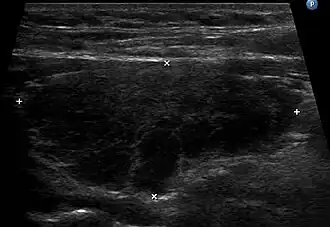

La tiroide presenta una straordinaria variabilità di peso e dimensioni che dipendono dall'età, dal sesso e dall'ambiente in cui si vive[3]. La morfologia della tiroide è fondamentale per la valutazione del suo status funzionale (nei pazienti normali questo status è definito "eutiroidismo") e si possono ottenere dati clinicamente rilevanti anche mediante tecniche non invasive. Degli esempi sono:

- Manovre manuali durante l'esame obiettivo del paziente (palpazione della tiroide);

- Tecniche ecografiche (ecografia della tiroide).[35]

Un'ecografia della tiroide può essere utilizzata per rivelare se le strutture sono solide o piene di liquido, aiutando a distinguere tra noduli e gozzi e cisti. Può anche aiutare a distinguere tra lesioni neoplastiche maligne e benigne.[88] Una biopsia con ago aspirato può essere eseguita per determinare con maggior precisione la natura di una lesione.[89] Quando sono richieste ulteriori esami di imaging può essere prescritta una scintigrafia tiroidea con somministrazione di iodio-123 o tecnezio-99m. Questo esame permette di determinare con precisione la dimensione e la forma delle lesioni, rivelare se i noduli o il gozzo sono metabolicamente attivi e rivelare e monitorare i siti di malattia della tiroide o metastasi al di fuori della tiroide.[90]